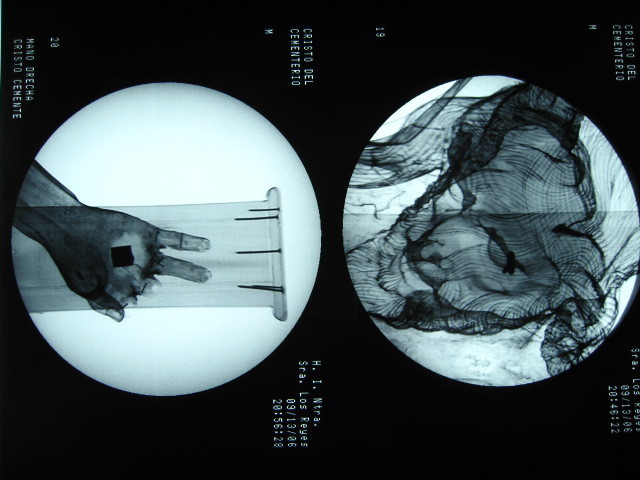

Echa un vistazo a esta galería de arte virtual en la que se pueden ver algunas de las restauraciones que he hecho. Quizá descubras algo que te interese durante la visita... o pienses en alguna obra de arte que sepas que está algo deteriorada, para que te hagas una idea de cómo podría quedar si se pone en buenas manos.